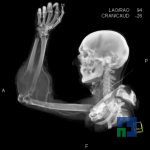

În cazul traumatismelor cranio-cerebrale:

- Diagnosticul edemului cerebral, a contuziei cerebrale, a leziunilor axonale difuze edematoase/hemoragice, a dilacerării cerebrale, a hematomului intraparenchimatos posttraumatic, a hematoamelor subdurale/extradurale (acute, subacute, cronice), a hemoragiei intraventriculare, a hemoragiei subarahnoidiene

- Diagnosticul traumatismelor de bază de craniu

- Diagnosticul fracturilor: